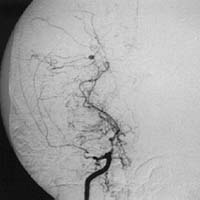

<³úÁöÁÖ¸·ÇÏÃâÇ÷>

<¼ö¼ú

Àü>

³úµ¿¸Æ·ù¿¡

ÀÇÇÑ ÁöÁÖ¸·ÇÏÃâÇ÷ÀÇ CT¼Ò°ß ¹× Ç÷°üÁ¶¿µ¼ú¿¡¼

Àü±³Å뵿¸Æ¿¡ µ¿¸Æ·ù°¡ º¸À̰í ÀÖ´Ù.

Àå¸é> <¼ö¼ú

ÈÄ>

¼ö¼ú

ÈÄ µ¿¸Æ·ù°¡ º¸ÀÌÁö ¾ÊÀ¸¸ç µ¿¸Æ·ù °æºÎ¿¡

Ŭ¸³ÀÌ µé¾î°¡ ÀÖ´Â °ÍÀÌ º¸À̰í

ÀÖ´Ù.